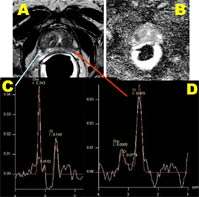

A: T2 Anatomic image

B: Applied diffusion coefficient

(tumor appears dark)

C: Abnormal spectroscopy

D: Normal spectroscopy

At UCLA, conventional prostate magnetic resonance imaging (MRI) is supplemented by a variety of related functional MR techniques such as the technically demanding technique of magnetic resonance spectroscopic imaging (MRSI). MRSI is a MR technique that enables detection and quantification of normal and cancer related chemical compounds in the human prostate gland. Although normal human prostate contains large quantities of citrate and low levels of choline, prostatic cancer contains lower levels of citrate and high levels of choline. The first successful demonstration of 1H MR Spectroscopy in distinguishing a variety of chemicals such as citrate, choline, spermine and creatine in human prostate was demonstrated by Dr. Albert Thomas and colleagues at UCLA in 1990. (JMR 1990).UCLA is a leader in the development and implementation in magnetic resonance spectroscopic imaging of the prostate with a dedicated team of scientists, radiologists, and technologists with two decades of experience.